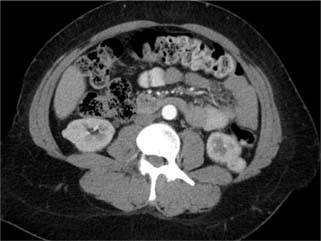

The third patient was 63 years old. He initially had a right enhanced renal mass (1.5 cm), accidentally diagnosed following an ultrasound for a vague abdominal pain. He elected for surveillance, and CT done after 1 year showed a stable right renal tumor and a new left renal tumor. Single-stage bilateral PN was done. Pathology showed bilateral ccRCC with negative margins. eGFR was stable at 12 months post-surgery. Figure 3 shows the bilateral renal tumors.

Figure 3: Third patient: bilateral renal tumor.